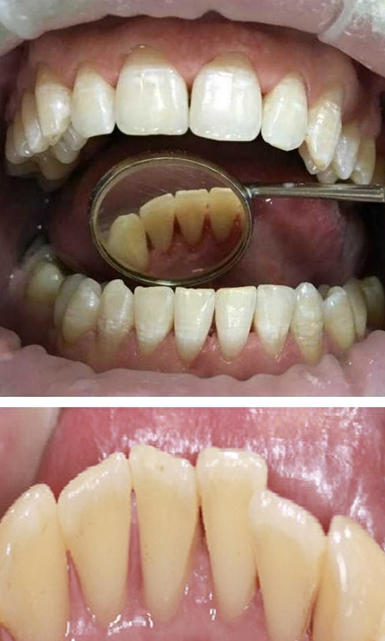

Профессиональная гигиена особенно важна при ортодонтическом лечении, ведь в повседневной жизни, дома, очень сложно поддерживать должный уровень гигиены полости рта! Даже если вы используете ирригатор и специальные ёршики! В нашей рубрике «до/после» вы видите то, что может быть с зубами при лечении брекетами, если не проводить своевременную чистку у врача-стоматолога. Марухно Дарья Александровна провела профессиональную чистку в несколько этапов, чтобы вернуть пациентке белизну ее собственных зубов! Брекет-система была поставлена не в нашей клинике, и почему пациентка не обратилась за профессиональной помощью раньше-вопрос) Но в данном случае, главное – итог! Кровоточивость после даже обычной чистки в такой клинической ситуации – естественный результат. Ведь обильный зубной налёт и зубной камень вызывают воспаление дёсен в виде гингивита, а порой даже пародонтита.

Доктор: Марухно Дарья Александровна